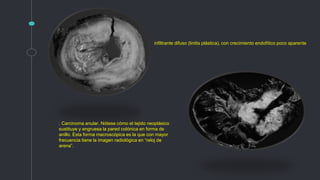

. Carcinoma anular. Nótese cómo el tejido neoplásico

sustituye y engruesa la pared colónica en forma de

anillo. Esta forma macroscópica es la que con mayor

frecuencia tiene la imagen radiológica en “reloj de

arena”.

infiltrante difuso (linitis plástica), con crecimiento endofítico poco aparente